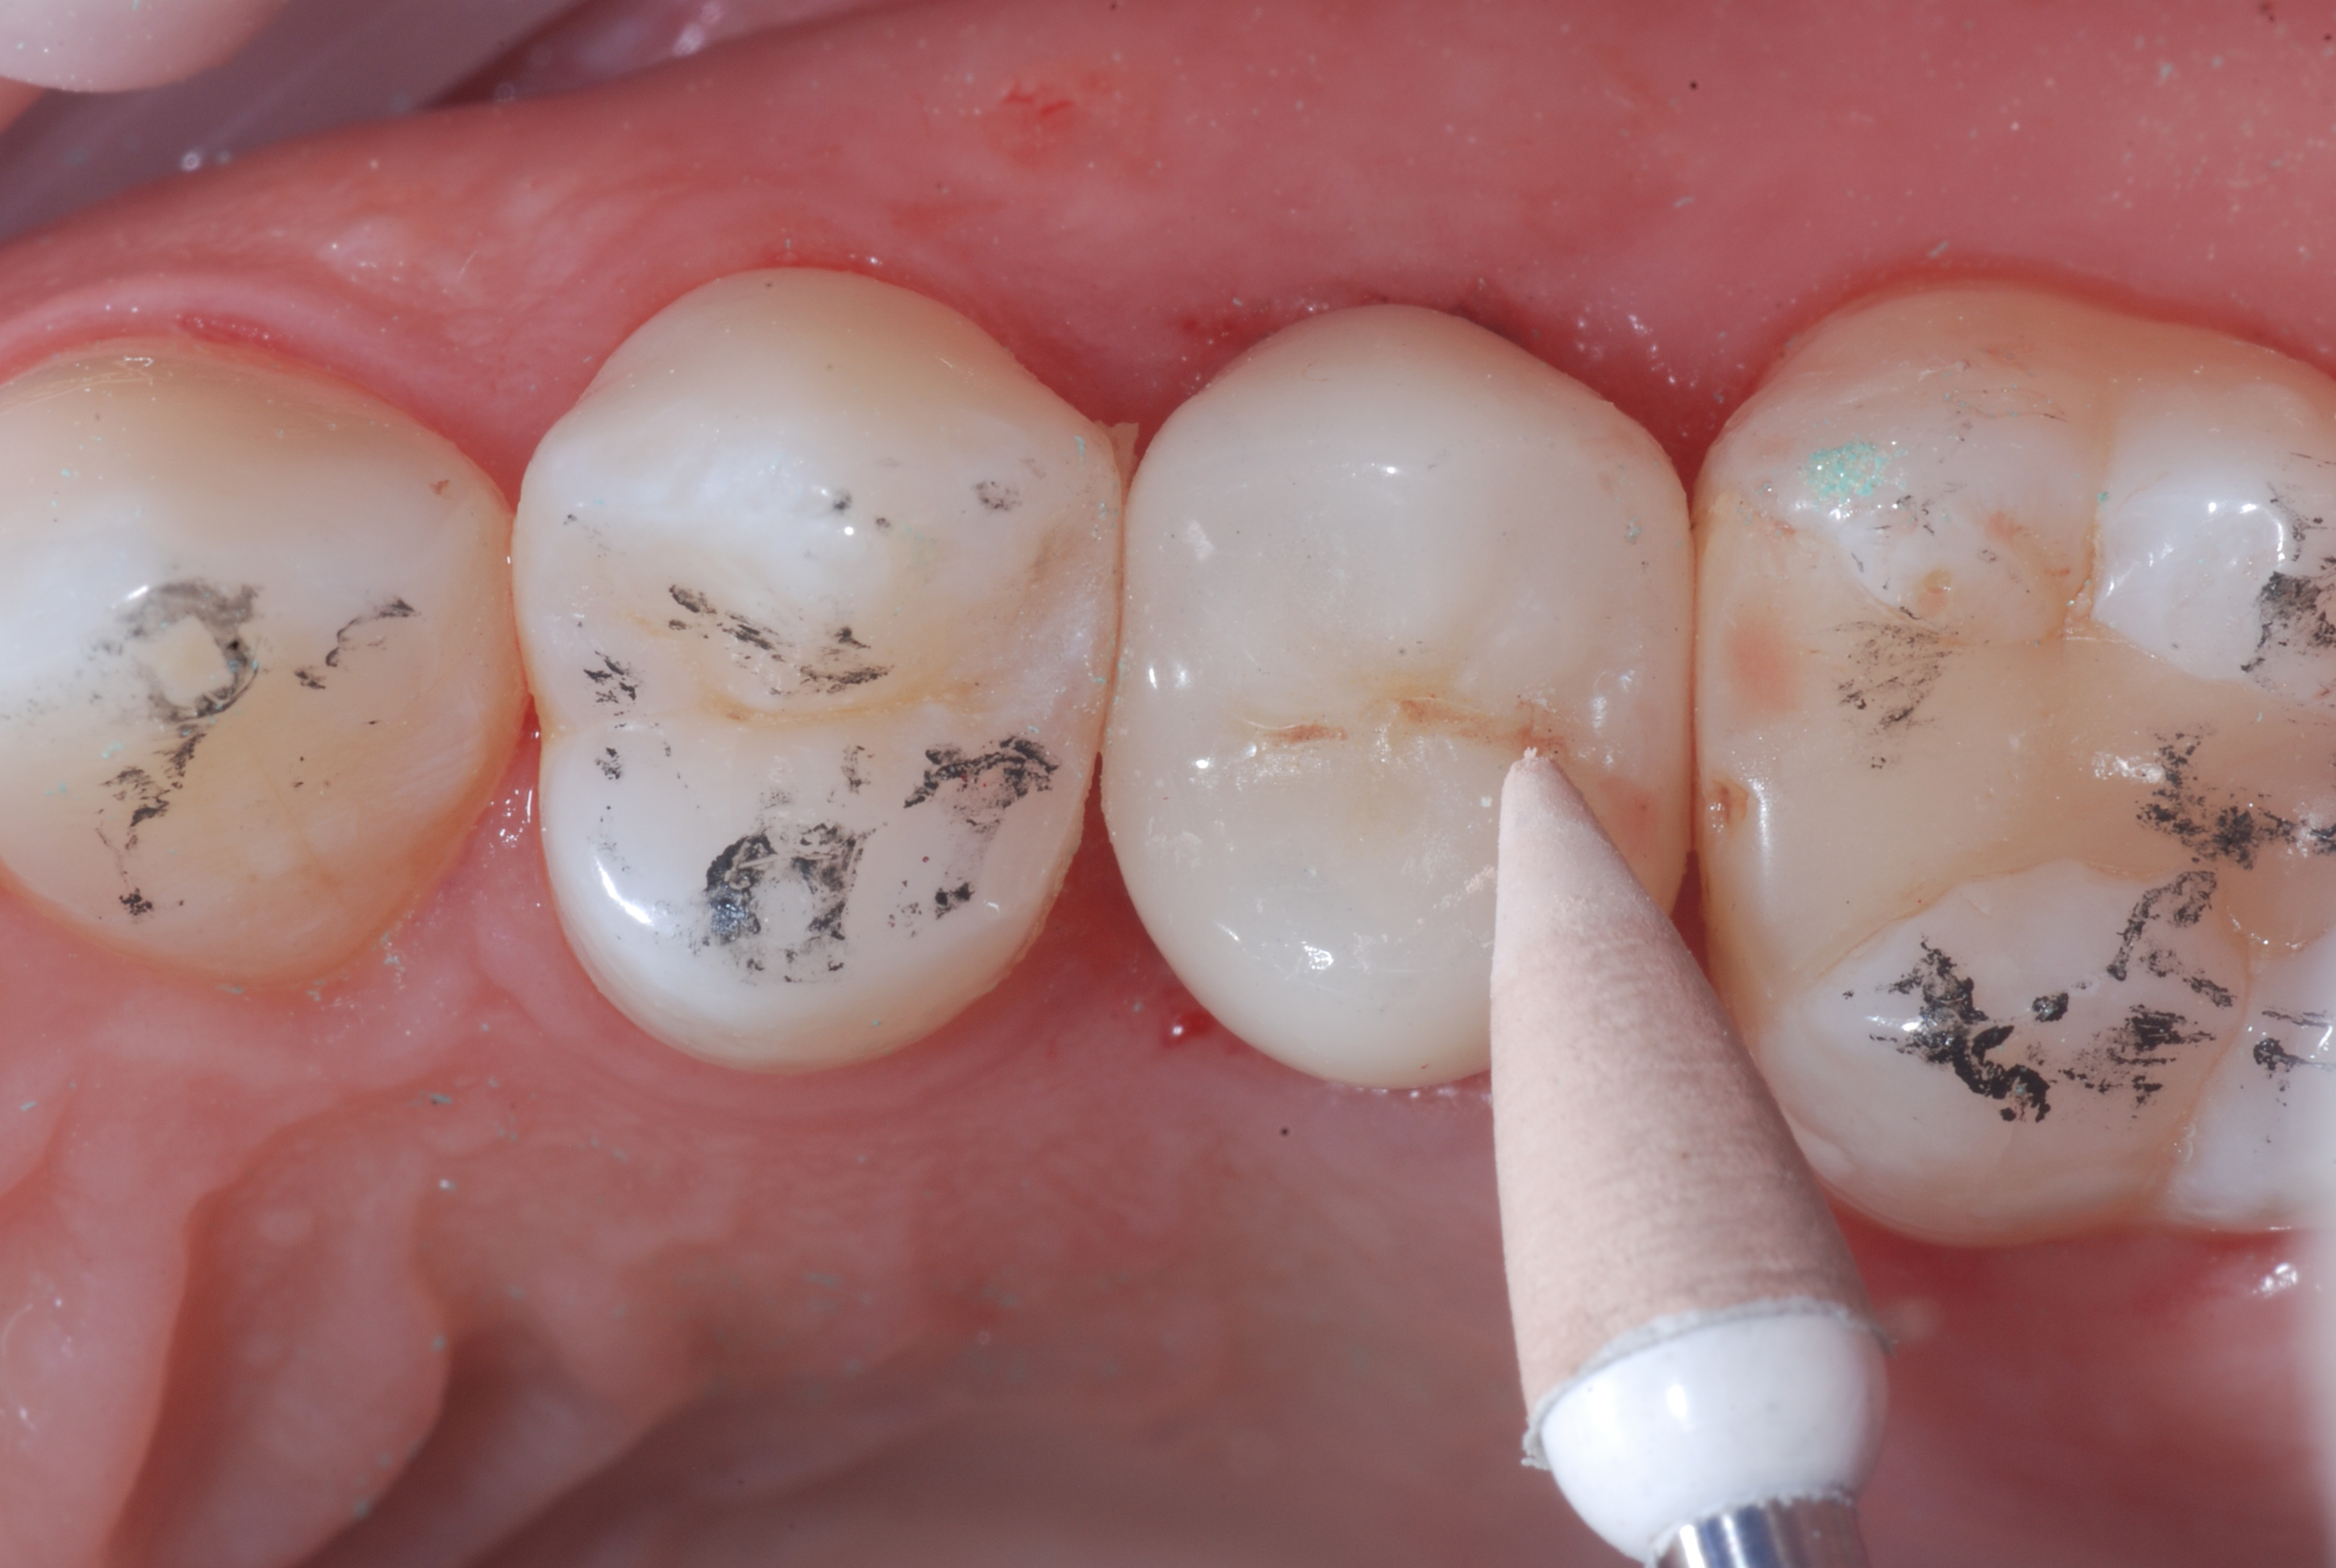

Figure 1

Figure 1. Bite Wing X-ray and Apical X-ray of tooth 25 completely compromised by the carious process.Figure 2. Clinical image of tooth 25 totally destroyed at the coronal level.

Figure 7. Milled lithium disilicate crown (Mr. Paolo Vigiani).Figure 8. The pass of the eZr Garrison coarse-grained blue rubber point immediately after cementation of the crown with a self-adhesive cement and occlusal adjustments made with a fine-grained diamond bur.

After the occlusal adjustment was performed with fine-grained diamond burs, the final polishing is carried out with eZr Garrison rubber polishers. The first step was performed with the coarse-grained blue rubber point to eliminate the microgrooves created by the diamond bur. Subsequently, the green medium-grained point was applied, which prepares the surface for the final polishing by the orange fine-grained point. Through these simple three steps, a perfectly smooth surface was obtained which is comparable to a glaze.  Unlike an unpolished surface which is rather abrasive for the opposing teeth, the mechanical polishing obtained with the eZr rubber polishers produces a shiny and an absolutely brilliant surface which is nonabrasive for the opposing teeth.

Figure 9. The pass of the eZr Garrison medium-grain green rubber point.Figure 10. The pass of the eZr Garrison finegrained orange rubber point.